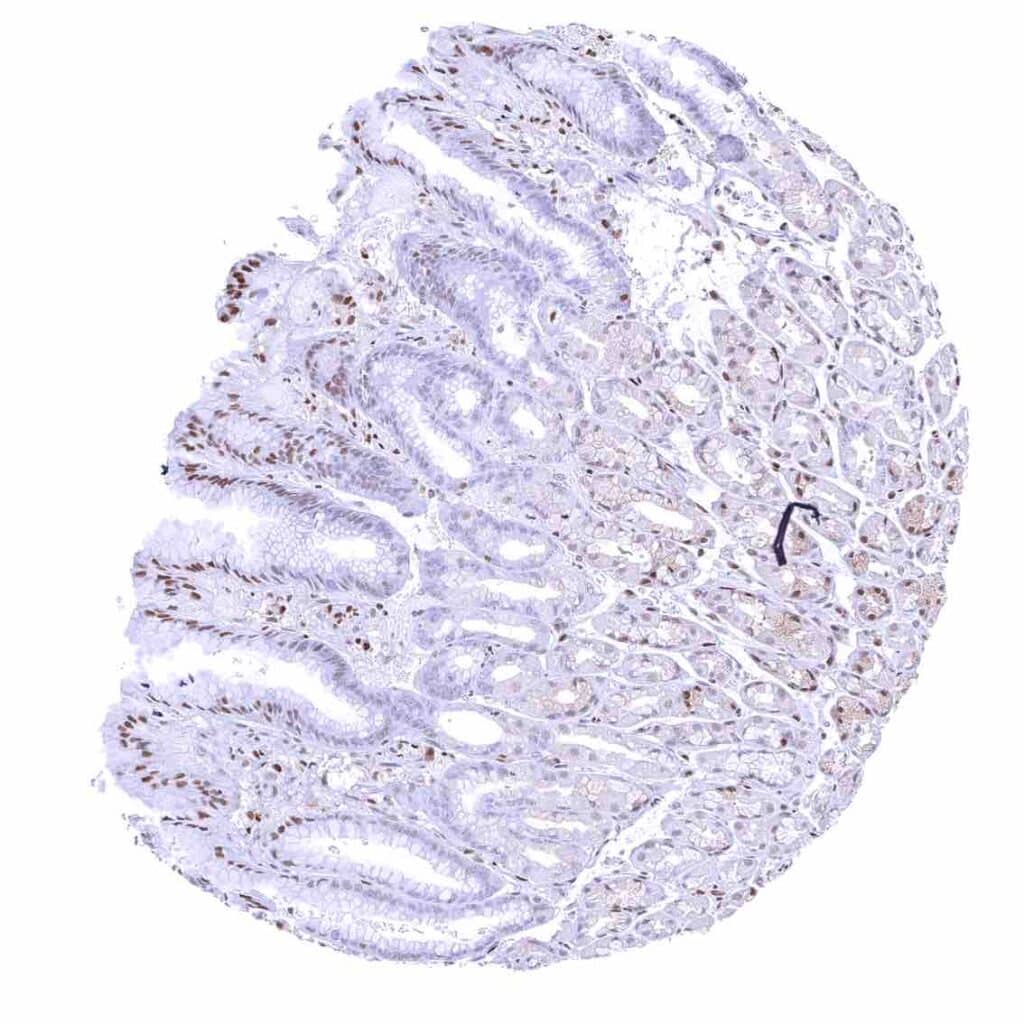

Colon descendens, mucosa

Duodenum, mucosa – Nuclear p27 positivity of a fraction of epithelial cells.

Ileum, mucosa – Nuclear p27 positivity of a fraction of epithelial cells.